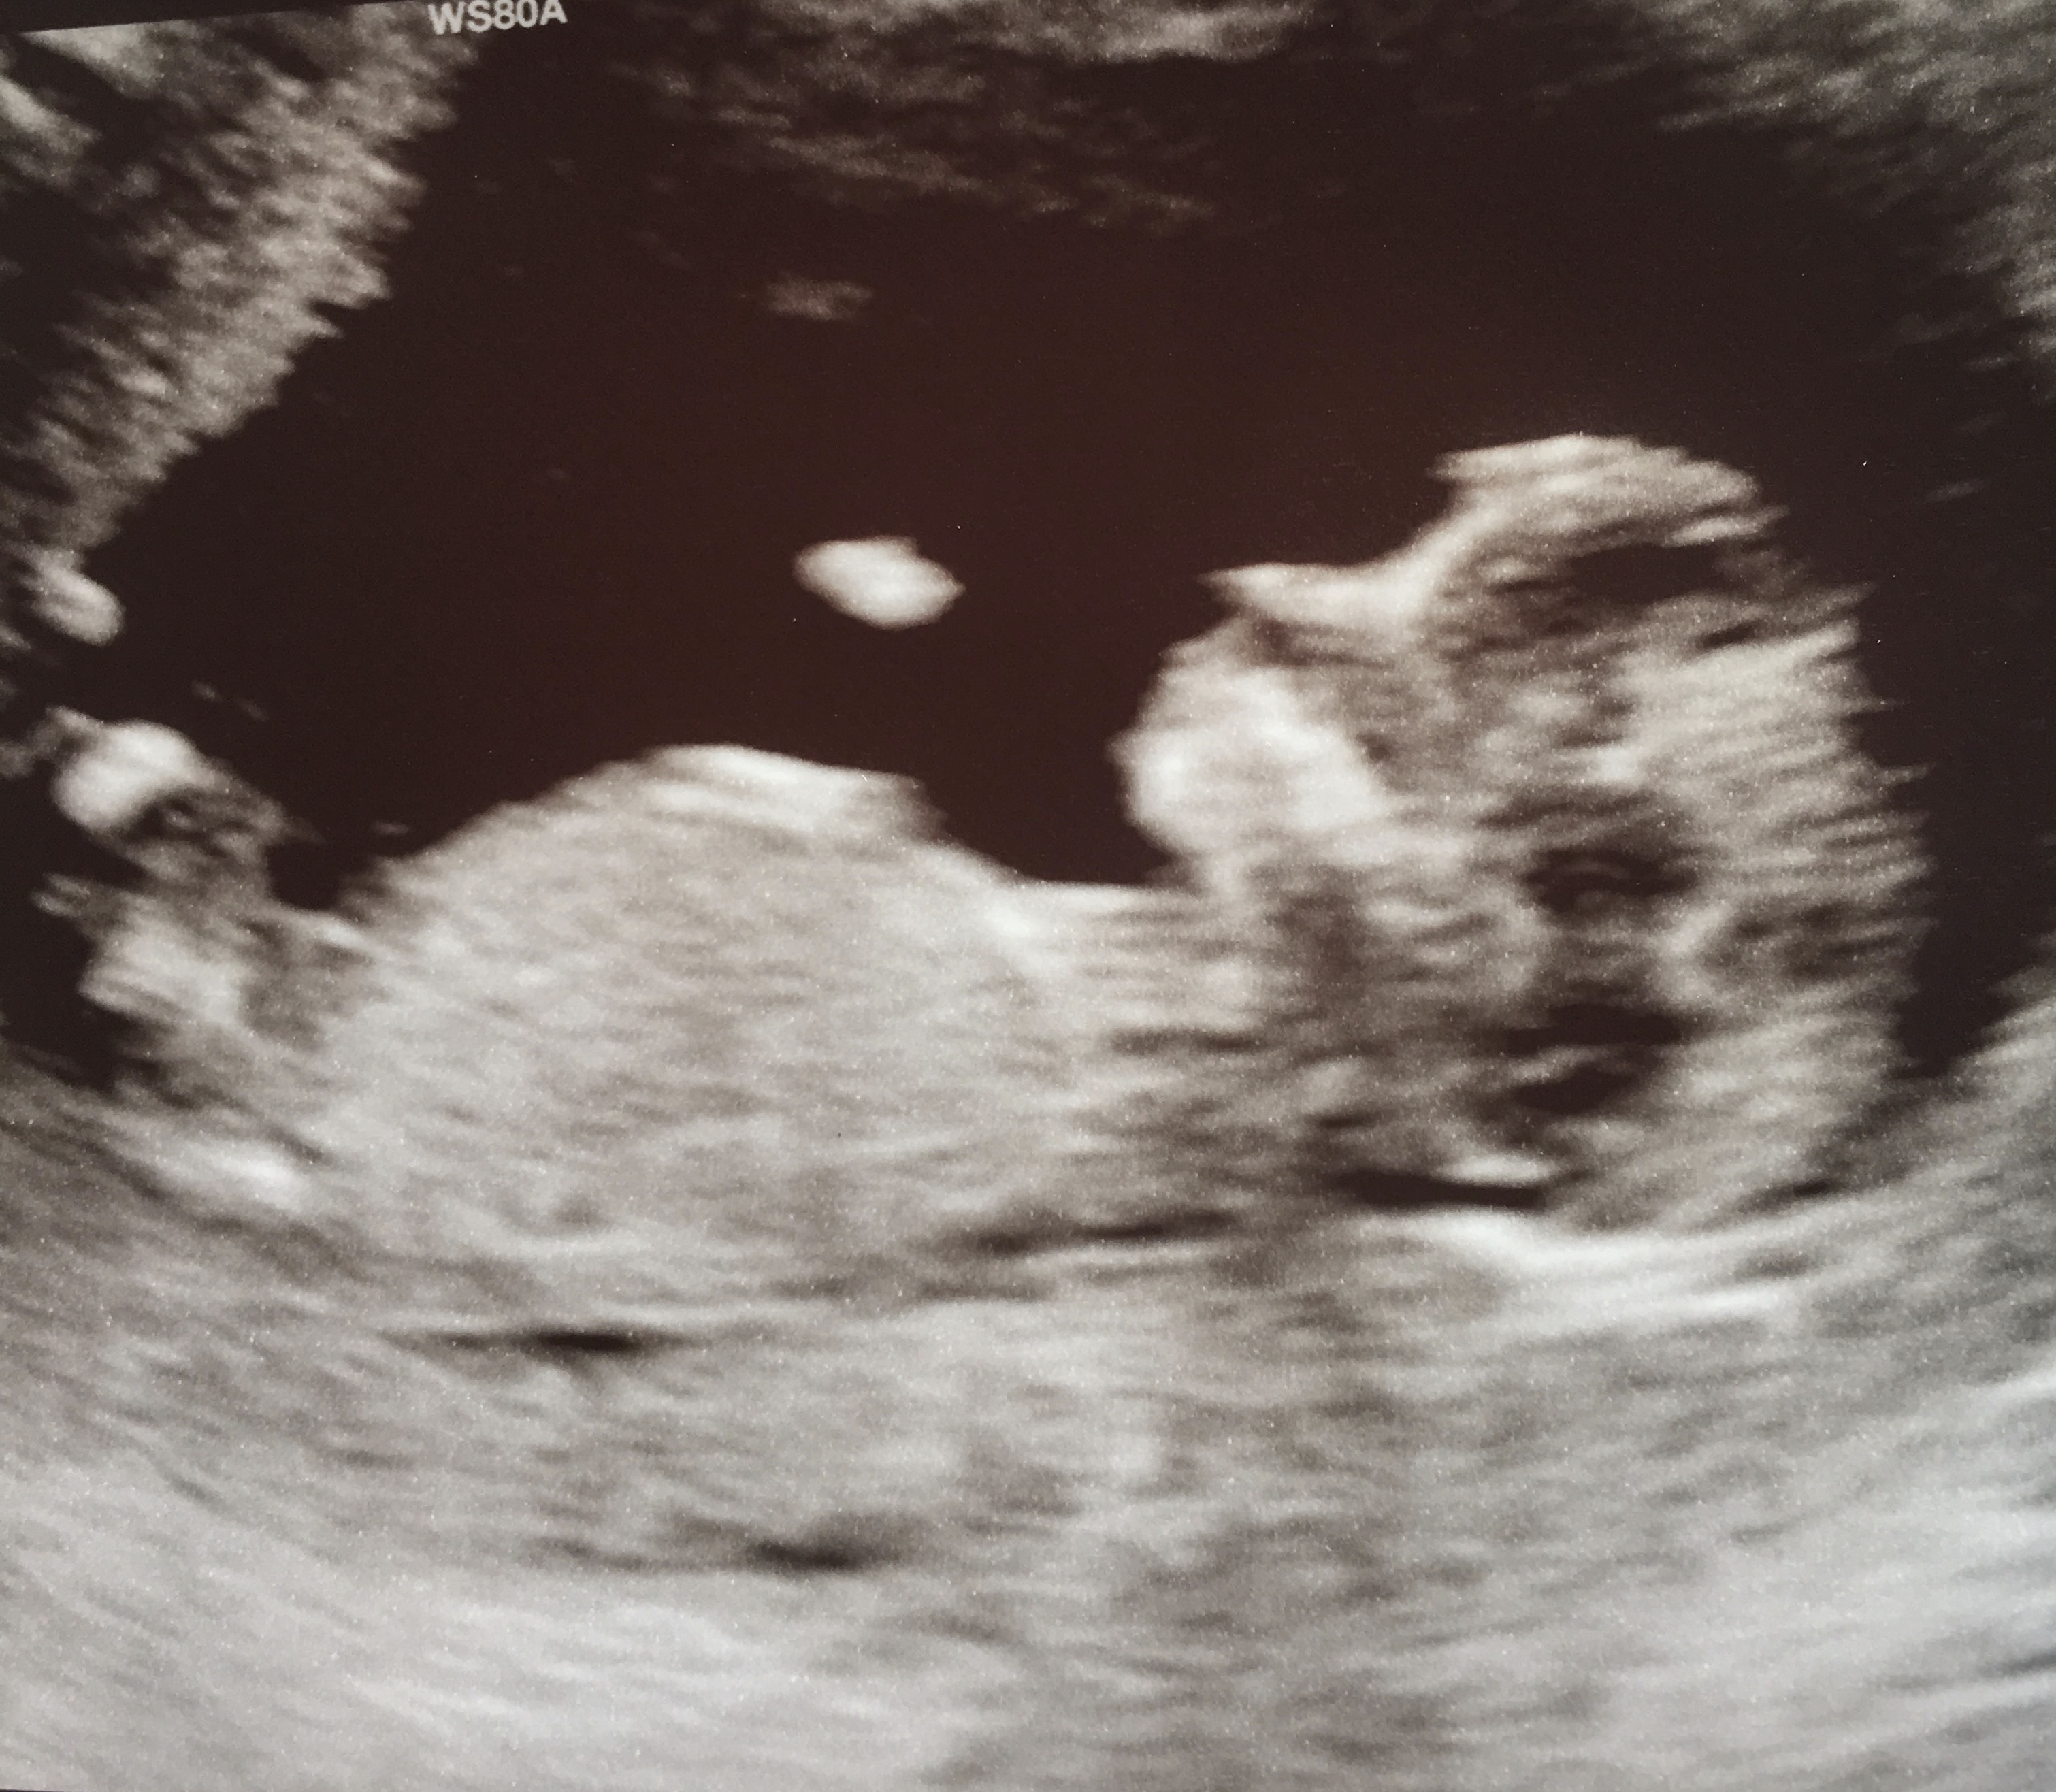

Forgot to mention... 13 weeks today

I'm not sure I see a nub, sorry.

If I am seeing a nub, I guess boy. But I am not really sure of what I am looking at.

Sorry it's a bit blurry and a lot going on in the nub area.